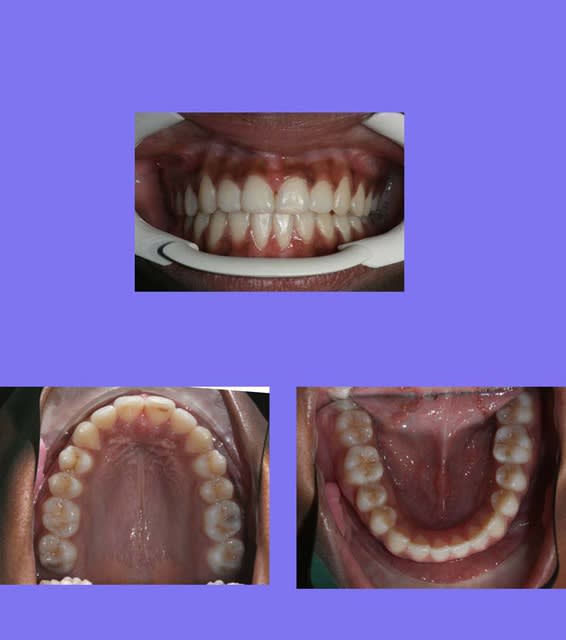

voici le cas terminé

@+ Bjc.